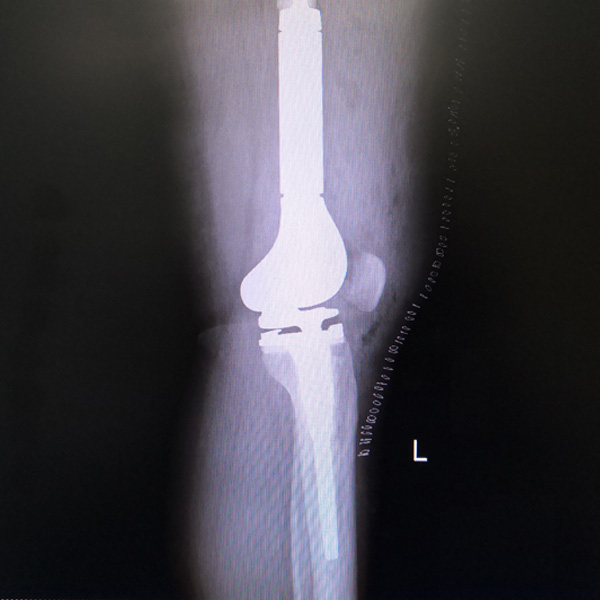

• 骨肉瘤手術骨肉瘤手術手術后手術前

骨肉瘤手術

患者張某,女,14歲,診斷為“左股骨遠端骨肉瘤”,當地醫院因為醫療技術和能力的限制,只能考慮截肢手術?;颊呒覍偻ㄟ^平臺推薦,指定到哈......